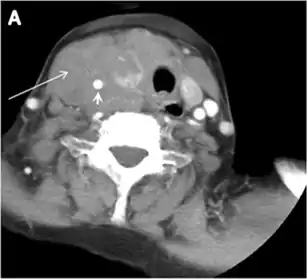

Thyroid lymphoma

Thyroid lymphoma represents about 5% of thyroid malignancies. Non-Hodgkin's lymphoma is the most common type and can be secondary to generalized lymphoma or a primary tumour. Primary thyroid lymphoma usually pre-exists with Hashimoto's thyroiditis. On CT scans with and without contrast, lymphomas tend to have low attenuation values. Thyroid lymphomas have a variable appearance and mostly manifest as a solitary mass (80%). They may also manifest as multiple nodules (15% to 20%) or as a bulky mass replacing the entire gland with extra-thyroid extension (Figs. 11 and and12).12). The presence of cervical lymphadenopathy supports such a diagnosis. Although it is uncommon, tumour necrosis has been reported.[1]

Fig. 11. Thyroid non-Hodgkin's large B-cell lymphoma in a 66-year-old female patient. an Axial enhanced neck CT scan demonstrates left thyroid lobe and isthmus homogeneously hypodense and minimally enhancing mass (white arrows). This lesion invades the prevertebral muscles (black arrows). Note the multiple enlarged level V lymph nodes (white arrowheads). b Post-treatment image shows significant reduction in size and mass effect of the left thyroid infiltrative mass, with almost complete resolution of the left cervical lymphadenopathy.[1] -

Fig. 12. Diffuse thyroid large B-cell lymphoma in a 79-year-old female patient. an Axial enhanced neck CT scan demonstrates a homogeneously hypodense and minimally enhancing large right thyroid solid mass (long white arrow) extending into the thyroid isthmus. It is encasing the right carotid artery (short white arrow) and displacing of the trachea and oesophagus to the left side.[1]